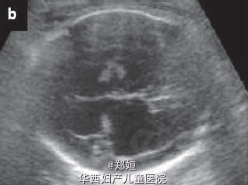

超声提示存活的那个胎儿有双侧的脑室扩大(11mm) 羊膜穿刺术提示核型正常 告知患者脑室增大提示宫内的胎儿死亡合并另一个神经系统损害 患者要求继续妊娠

复查超声,提示存活的胎儿脑皮质变薄,怀疑脑穿孔 孕28周MRI检查提示脑穿孔性囊肿 孕41周自然生产3.1kg女婴 胎盘肉眼可见死亡的一胎紧贴胎盘 胎儿MRI提示双侧脑实质局灶性损害 MR造影提示双侧的大脑中动脉阻塞